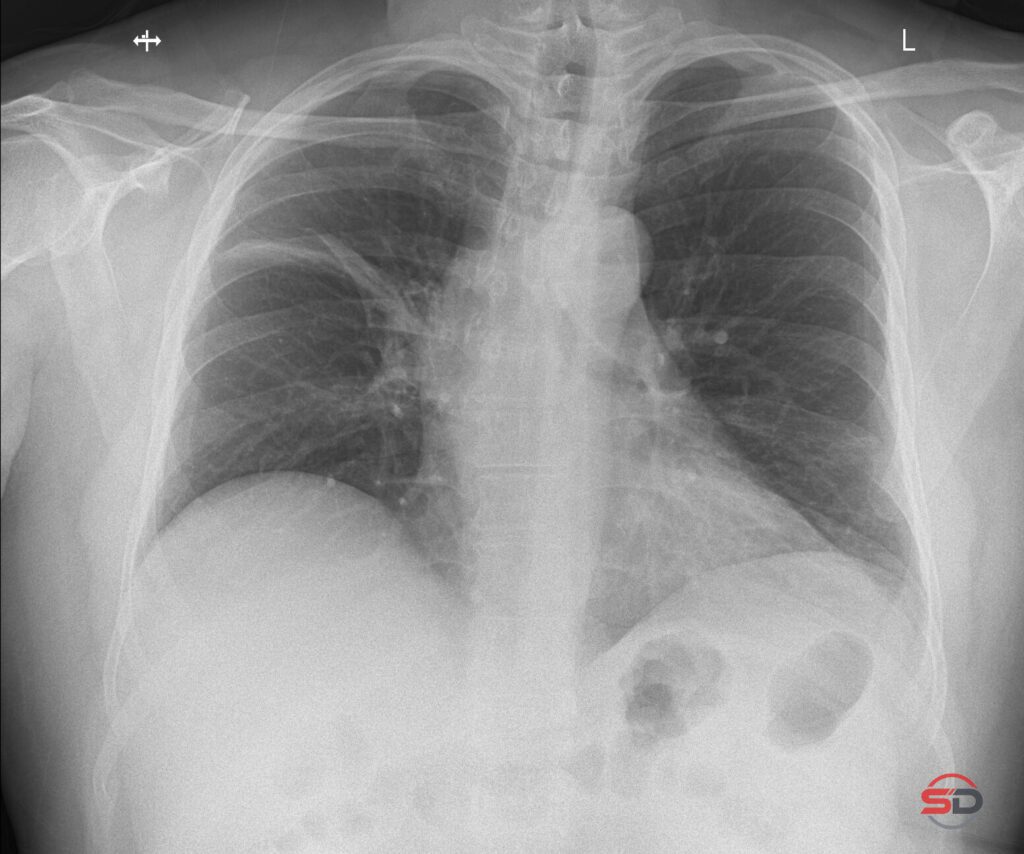

Wie zuverlässig sind Grössenmessungen im Thoraxröntgen?

Das konventionelle Thoraxröntgen gehört zu den am häufigsten durchgeführten radiologischen Untersuchungen. Neben der Beurteilung des Lungenparenchyms, der Mediastinalstrukturen und des […]